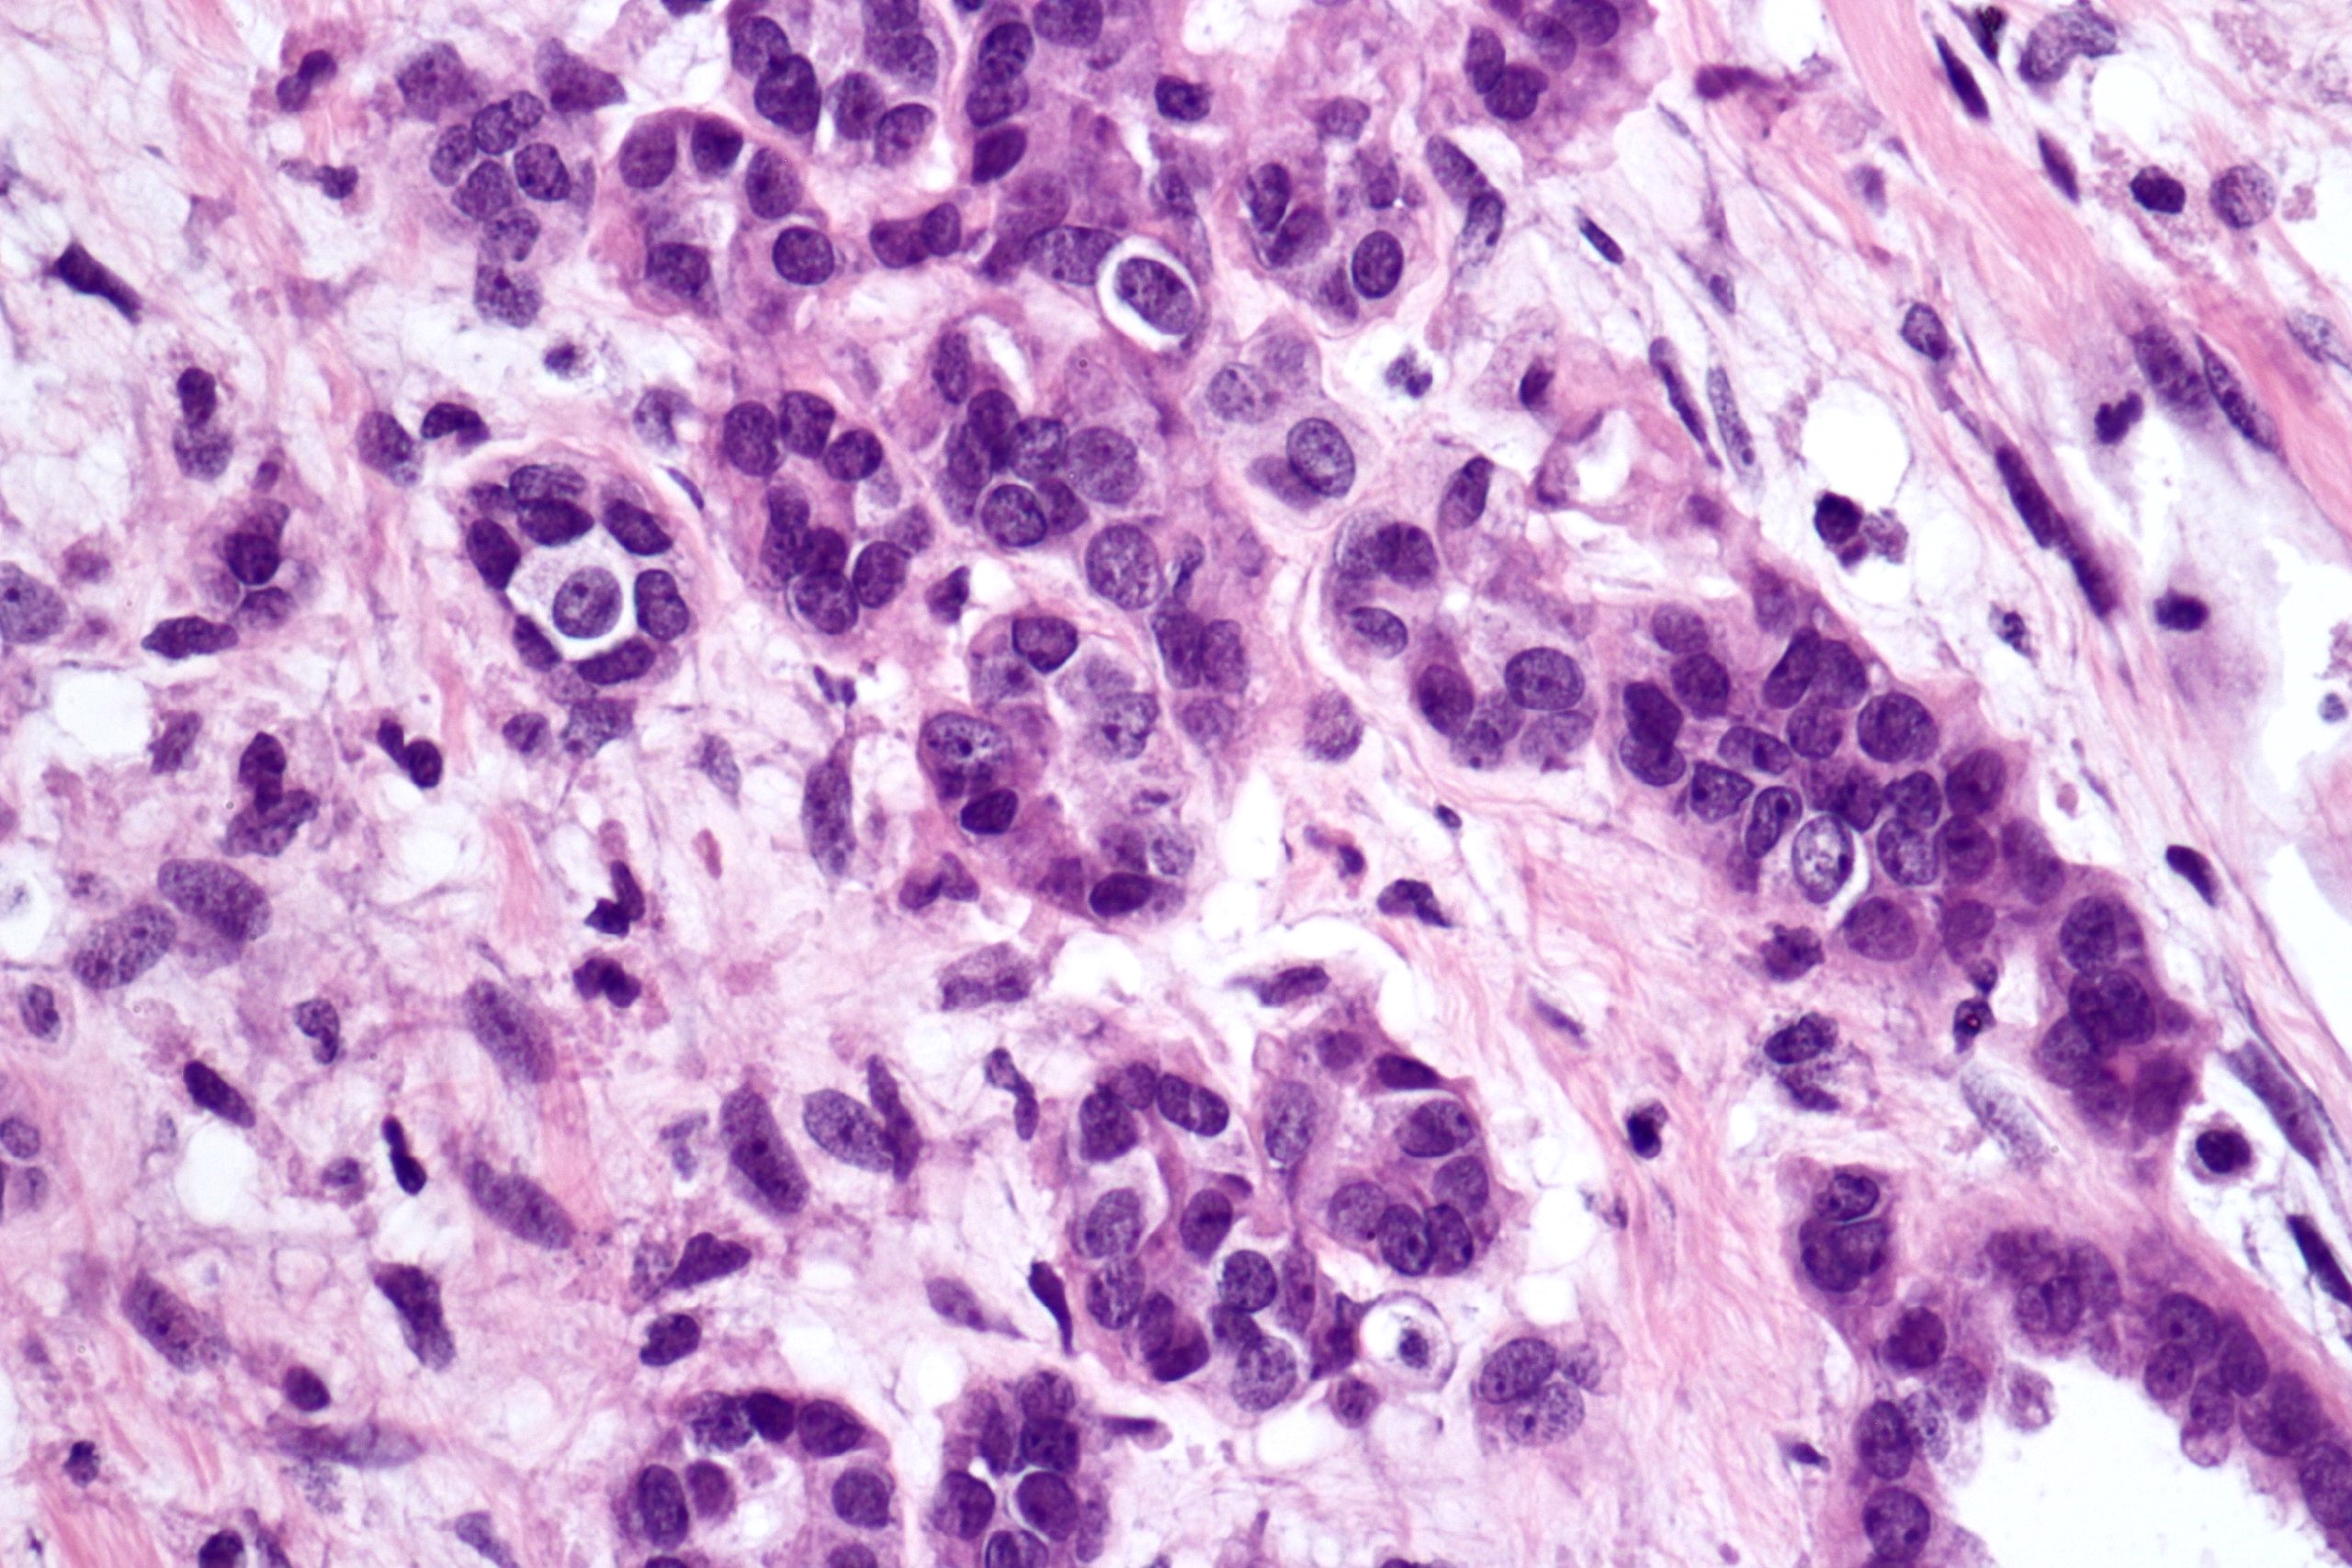

Microscopic (histologic) description

- Cysts lined with flat / cuboidal / hobnail cells (or are denuded)

- Epithelial elements consist mainly of mature and immature / abortive tubules and small papillae resembling immature glomeruli

- Key histological findings of the variably cellular septa include

- Nephroblastomatous epithelial elements

- Islands of undifferentiated blastema and differentiated mesenchymal elements (skeletal muscle and less often cartilage and fat) (J Urol 2010;183:1585)

- Focally, the septal elements may protrude into the cystic spaces in microscopic papillary folds

Microscopic (histologic) images

Contributed by Americo Brilhante, M.D. and Daniel Athanazio, M.D., Ph.D.